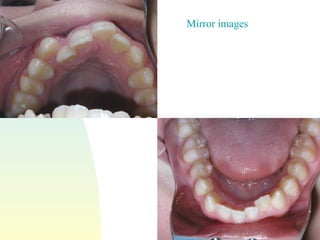

Mirror images